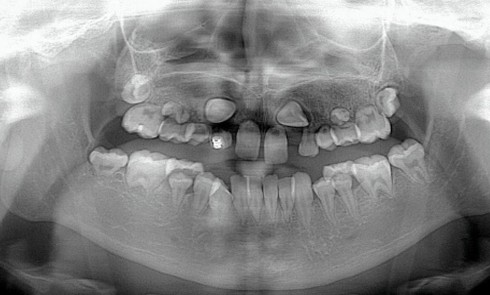

Article réservé à nos abonnés Gestion prothétique d’une adolescente traitée par radiothérapie et chimiothérapie durant l’enfance. À propos d’un cas

Cet article présente la prise en charge d’une jeune patiente ayant un antécédent de sarcome d’Ewing traité par chimiothérapie, chirurgie...